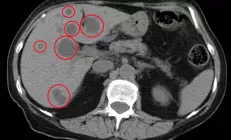

УЗИ органов брюшной полости;

по показаниям: КТ, МРТ, МРХПГ (визуализация билиарного дерева)